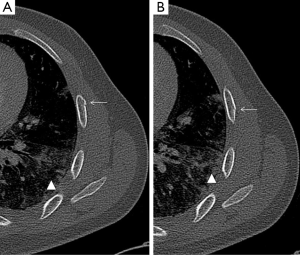

A nondisplaced rib fracture is defined as a rib fracture with complete cortical disruption but with maintained alignment, usually involving the medullar bone and both the inner and outer cortices (Figure 1); it is seen such a lucent line on radiographs or CT images (14). Stress rib fractures are overuse injuries that occur when there is an abnormal force on normal underlying bone. These begin with a small stress on the bone, which with repeat injury results in a microtrabecular fracture that may progress to rib fracture. These injuries are rare, although possibly underdiagnosed, and most often seen in workers who perform repetitive motions and athletes. Detection of non-displaced and stress rib fractures on radiographs is difficult, and these injuries may be seen radiographically only at follow-up imaging, after signs of healing have manifested (7). On the contrary, MRI can show immediately an area of oedema (high T2 signal) after a traumatic event. When cortical disruption and a substantial abnormality in alignment are evident, a rib fracture is classified as displaced. Displacement may be minimal or obvious. Displaced fractures may be identified on radiographs or CT images (Figure 1). Injury to the surrounding tissues and structures can occur, and several lethal complications such an aortic injury have been documented in the literature (15). A buckle fracture of the rib occurs when there is disruption of either the inner or outer cortex (Figure 2) with no observable fracture of the other cortex (16). Some researchers have reported that the term buckle is derived from engineering terminology that describes disruption of the inner or tensile side of a structure that is placed under force (7,17). Flail chest (“volet”) is a traumatic condition in which there are three or more contiguous ribs with fractures in two or more places (Figure 3). Fractures usually occur in the anterior and anterolateral portions of the middle to lower ribs (1). These fractures create a flail segment that can move paradoxically relative to the remainder of the chest during respiration in a spontaneously ventilating patient. Although imaging can show fractures, it is the clinical examination that will demonstrate paradoxical motion. Flail chest serves as a marker for significant intrathoracic injury, since more than one-half of the affected patients may have associated injuries that require surgical treatment (18).